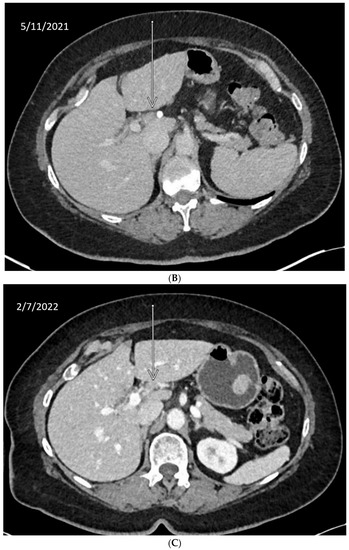

10. Anecdotal Case of RAD51 Mutation in CCA

| BAP1 | Involved in chromatin modulation and transcriptional regulation. It localizes in the endoplasmic reticulum, where it binds, deubiquitylates, and stabilizes IP3R3, modulating calcium release from the endoplasmic reticulum and apoptosis [44]. In HR, it regulates and recruits key downstream effectors, including p53, BRCA1, and RAD51. It is phosphorylated by ATM [45]. | 7.4% | Case report: Patient with refractory metastatic CCA with novel BAP1 mutation (splice site c.581-17_585del22) had a good, prolonged response to olaparib (>11 months) [46]. Clinical: Rucaparib in patients with BAP1-deficient (by immunostaining) or BRCA1-deficient recurrent mesothelioma showed early signs of efficacy (disease control rate at 12 weeks was 58%) [47]. |